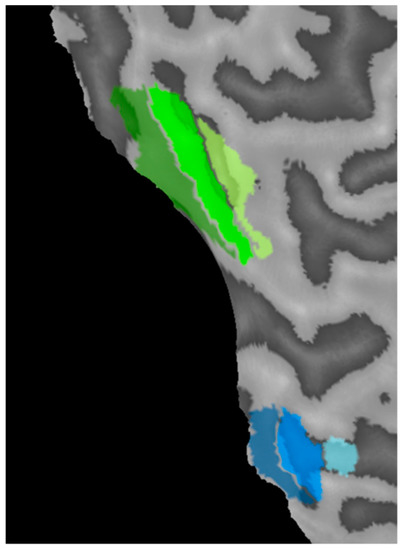

| Participant | Age | Type | Refraction | Acuity | Deviation | History, Stereo | Data Point |

|---|---|---|---|---|---|---|---|

| AR | 47/M | RE LE strab | Ø Ø | 20/20 20/50 | XT 1° | Detected age 6 y, no patching, no surgery, no stereopsis | ![]() |

| RD | 49/M | RE LE strab | +3.00 DS +4.00 DS | 20/15 20/125 | ET 1° | Detected age 6 y, glasses 6 y, no other treatment, local stereopsis (200 arcsec) | ![]() |

| GN | 30/M | RE mixed LE | +5.00–0.00 × 120° +3.50–1.00 × 75° | 20/70 20/20 | ET 8° | Detected age 2 y, strabismus surgery ages 2–6 y, no stereopsis | ![]() |

| JG | 21/M | RE LE strab | −2.00–0.50 × 150 −1.00 DS | 20/20 20/100 | ET 3° | Detected age 5 y, patching for 3 y, no surgery, local stereopsis 200 arcsec | ![]() |

| AS | 21/F | RE LE strab | Ø −0.5 DS | 20/160 20/20 | ET 15° | Detected age 4 y, patching at 4 y for 6 m, surgery at 7 y, no stereopsis | ![]() |